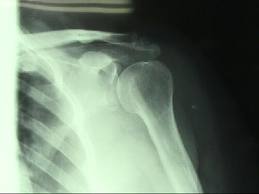

肩

から転倒

。

ハッ

と起き上ったら肩が、

ぷら~ん

ぷら~んと外れてました。

検査の結果、脱臼

と骨にヒビ

が入っており、

2-3週間は戦線離脱です